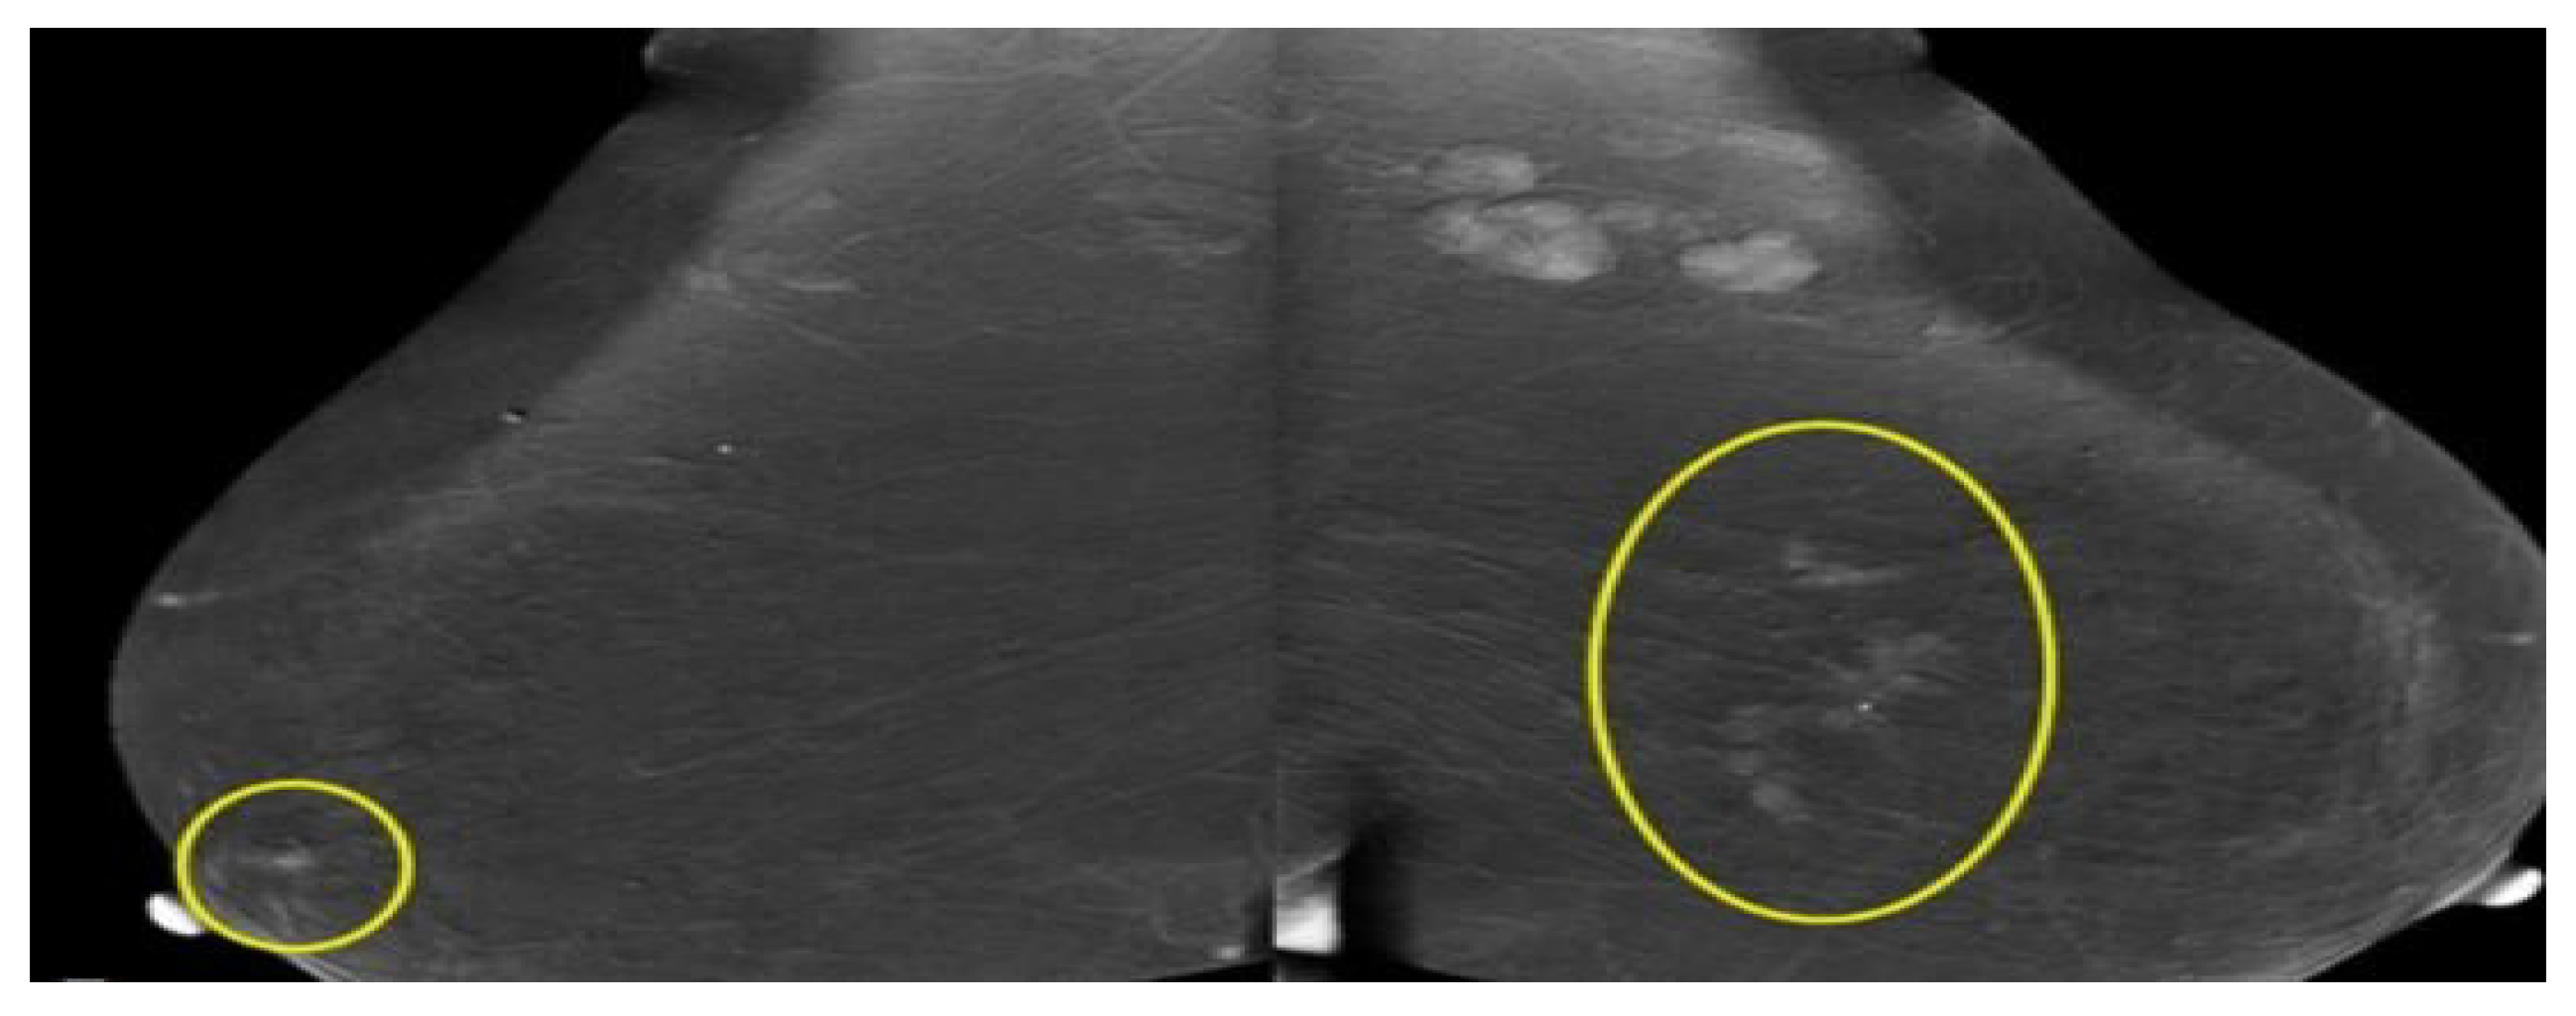

Mammogram, also called mastography, is a low-dose energy X-ray (ionizing radiation) procedure to produce images (radiographs) of the breast. It can be used to screen or diagnose people who are symptomatic (have symptoms of illness) or asymptomatic (have no symptoms of illness) [39]. Ordinary radiation dose around 0.4 millisieverts (mSv) or 30 peak kilovoltage (kVp) for two views of each breast [40,41]. 2D mammograms only compress the breast and catch images from the front and side. 3D mammography (or called tomosynthesis) produces X-ray images of the breast by taking various views across the breast in an arc. Previous studies reported that the detection is significantly improved when 3D mammography was used with 2D mammography [42]. A mammography expert, often known as a mammographer, performs this process. A mammographer is well-trained to take X-ray images of the breast. The radiologist specializing in reading medical imaging tests will review the mammogram to search for unusual configurations that look different from normal tissues. It can be representing a cancerous tumor, non-cancerous masses or cysts. Breasts are compressed between two firm surfaces to separate overlapping breast tissue and to reduce the thickness of the breast during the procedure. Then an X-ray produces black-and-white picture of breasts that are appear on a computer screen and examined by a radiologist that looks for signs of cancer, as shown in Figure 5 and Figure 6. A mammogram is not suitable for women with denser breast and more likely to have false alarms due to the overlap of normal fibro-glandular tissues [43,44,45].

Figure 5.

Samples of Mammogram breast image [46].

Figure 6.

Conventional mammogram of breast cancer [46].